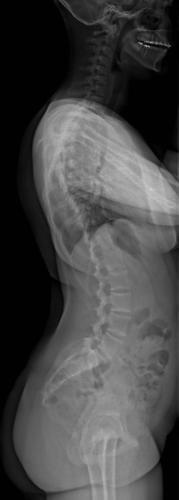

Images de scolioses opérées 16 janvier 202418 janvier 2023 par Damien Scoliose Thoracique 2 Scoliose thoracique Droite - cliché pré-opératoire de Face Scoliose thoracique Droite - cliché pré-opératoire de Profil Scoliose thoracique Droite - cliché post-opératoire de Face Scoliose thoracique Droite - cliché post-opératoire de Profil